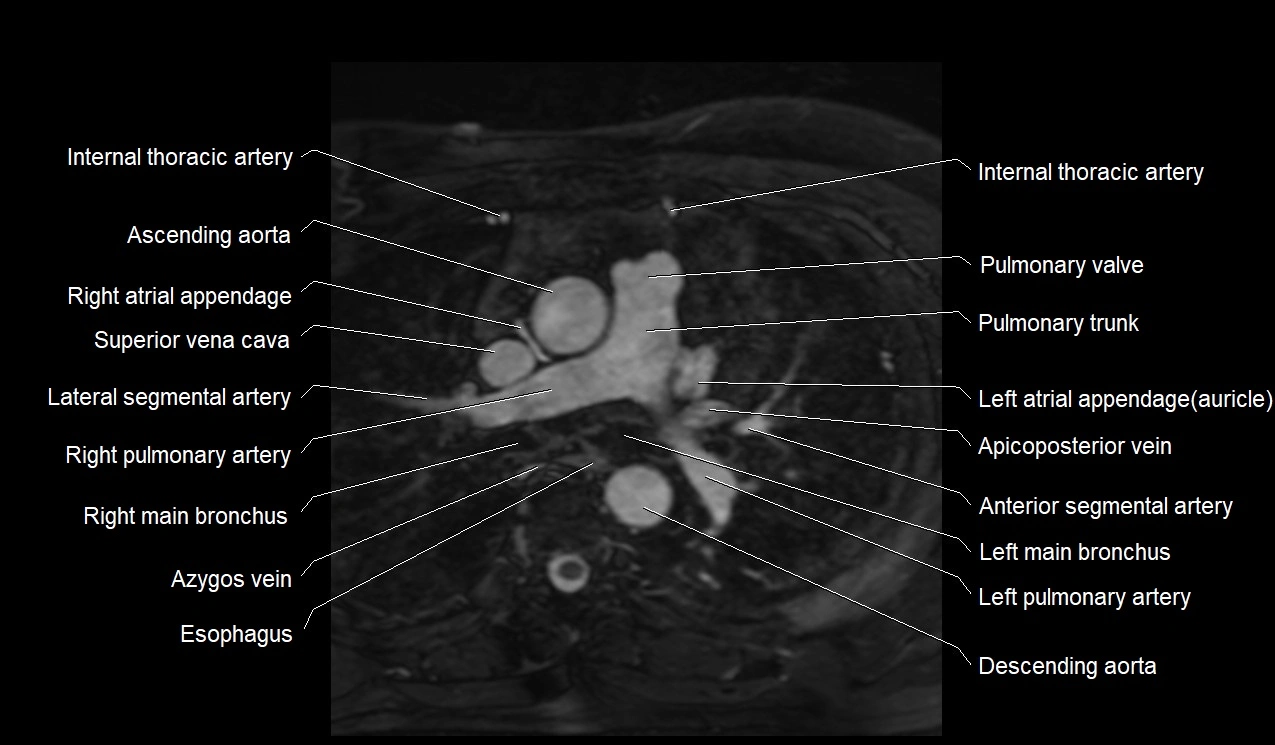

MRI image